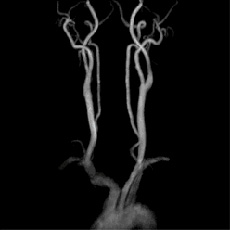

• 頸部MRA右内頸動脈50%狭窄

右内頸動脈50%狭窄